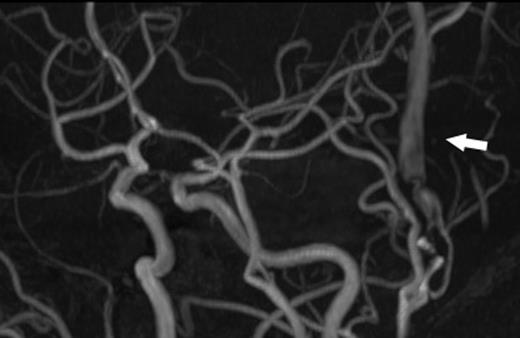

A 24-year-old male was admitted to our hospital after a traffic accident. Computed tomography scan had shown an acute epidural hematoma on the right surface of frontal lobe, which was emergently treated by surgical evacuation. One month later, he began to complain of pulsatile tinnitus in the left ear. A head magnetic resonance angiogram showed an extremely dilated vein in the left temporal region (Fig. 1). An angiography revealed a direct shunt between the left parietal branch of the STA and the superficial temporal vein (STV) in the preauricular region as well as an aneurysm in the left frontal branch of the STA (Fig. 2). He underwent surgery to remove the AVF and the aneurysm (Fig. 3). Pulsatile tinnitus disappeared immediately after surgery. Histopathological examination demonstrated that the artery was connected to the vein through the thin-walled vessels lacking internal elastic lamina and muscularized media, suggesting that the connecting vessels were newly formed (Fig. 4).

Left external carotid arteriography showed a high-flow AVF from the parietal branch of the STA (thin arrow) to the STV (wide arrow), and an aneurysm on the frontal branch of the STA (arrowhead).